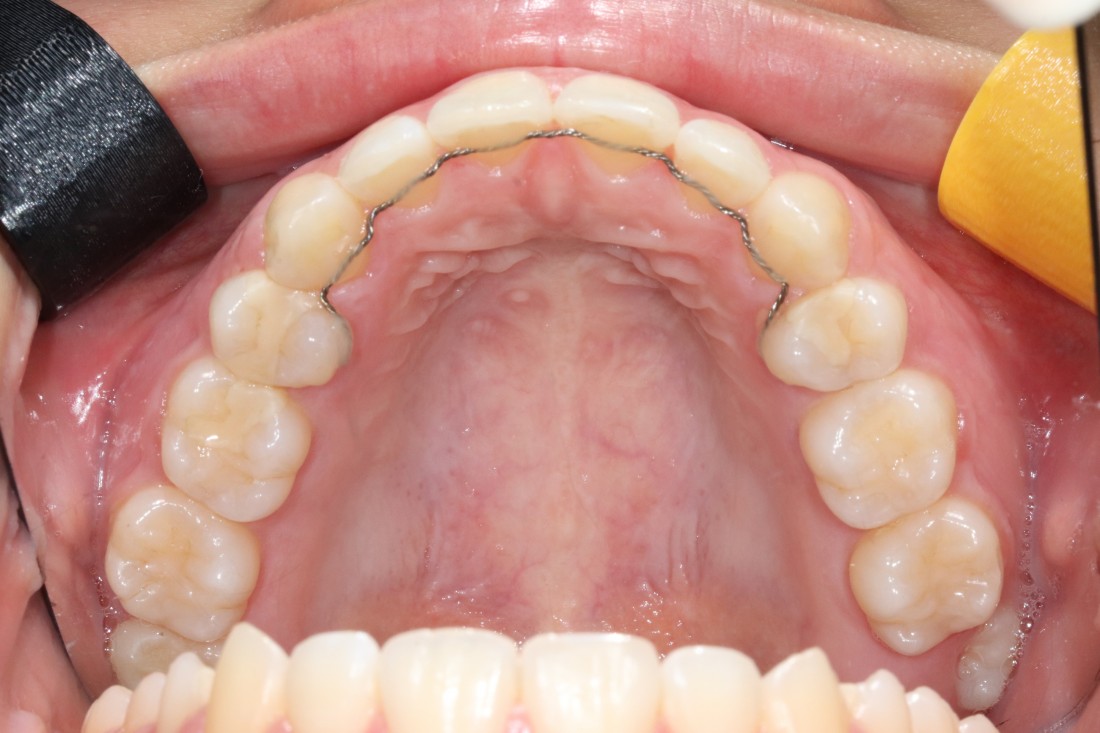

![]() | ![]() |

광주 교정치과에서는

발치교정 역시

전문의 치아발치를 통하여

전문적인 교정진료를

제공하고 있습니다.

발치교정, 비발치교정을 결정하는 것은

교정 전 3차원 105항목 정밀검사를 통해

교정전문의 대표원장님과의

세심한 상담을 통해 정하게 됩니다.

무조건 비발치 교정만이 좋은 것은 아니며,

개인차에 의해 발치교정이 필요한 경우에는

발치교정을 통해 원하는 교정치료 결과를

얻을 수 있습니다.